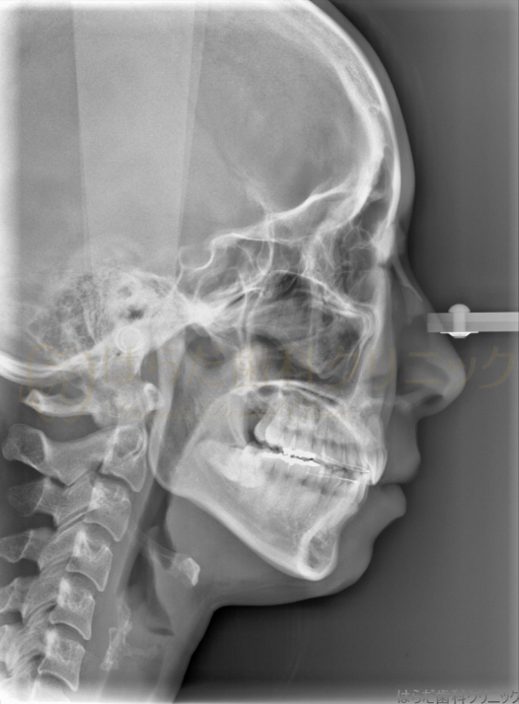

舌側矯正の症例紹介

After

主訴

上下の歯並びが気になるけれども矯正器具が目立つのも気になる

治療内容

舌側矯正

スペースを確保するため上下左右4番目を抜歯いたしました。

その後、全体的に歯の裏にて矯正をいたしました。

今回使用した矯正装置はメタルブラケットになります。